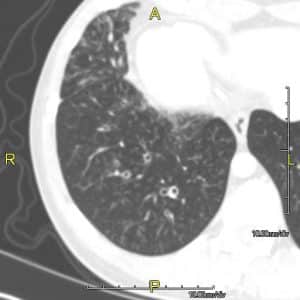

In the chest, this causes problems with mucociliary clearance leading to increased susceptibility to low-grade infections and irritation from foreign particulates. Figure 2 demonstrates a CT scan of a patient with PCD.

Figure 2: A CT scan of a patient with PCD showing mild bronchial wall thickening

- High resolution CT (HRCT) is the gold-standard investigation to diagnose bronchiectasis. Features indicative of the diagnosis are; bronchial wall thickening, diameter of bronchus larger than that of the accompanying bronchial artery (‘Signet ring’ sign) and visible peripheral bronchi.

- Different patterns seen on HRCT can occur with different aetiologies

- Bilateral upper lobe bronchiectasis is commoner in CF.

- Unilateral upper lobe bronchiectasis is commoner post-TB infection.

- Focal bronchiectasis (lower lobe) can be seen after foreign body inhalation.